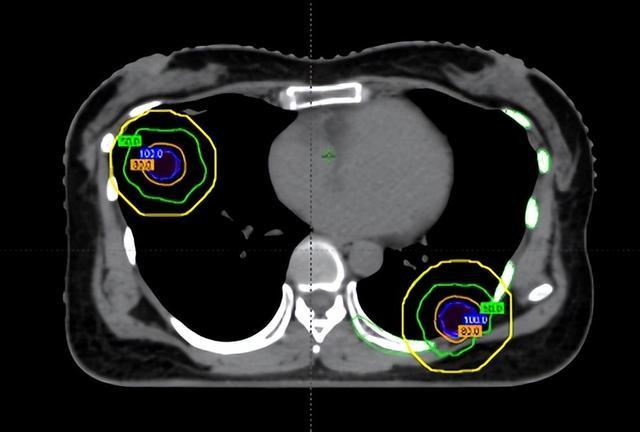

在维持前,团队通过四维CT对三个病灶进行精确定位,尤其是紧贴肋骨的阿谁病灶,连与肋骨之间极其微弱的裂缝齐被明晰标注出来。

随后参加最中枢的剂量狡计局势。胡英评释注解与李忠伟、雷大明物理师反复推演射澄清径和强度分散,把高剂量区域严格戒指在肿瘤鸿沟内,同期让剂量在极短距离内飞速下跌。不错清醒为,快乐飞艇在体内完成了一次“毫米级雕塑”:肿瘤被精确遮盖,而近在目前的肋骨却被保护在安全鸿沟内。